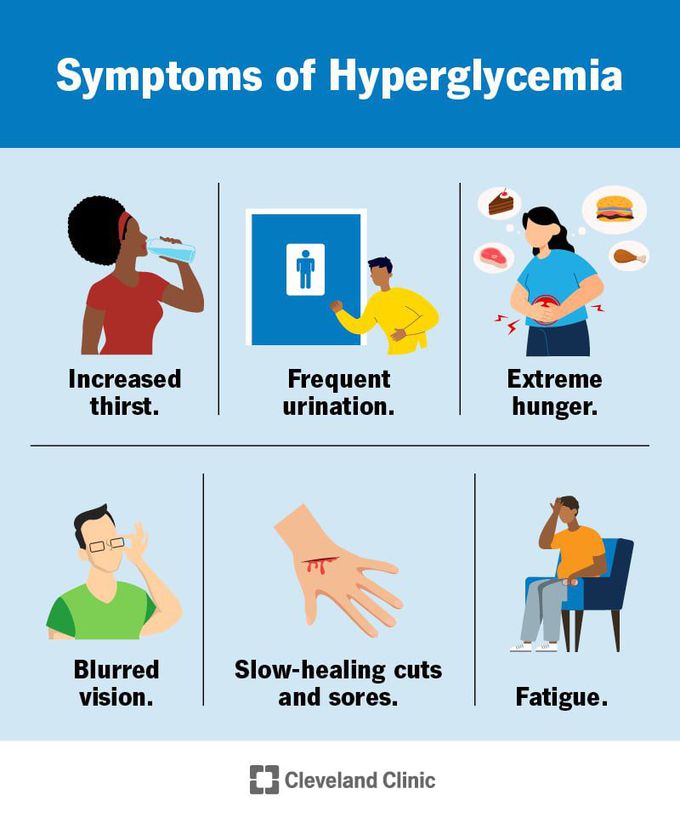

Symptoms Of Hyperglycemia MEDizzy